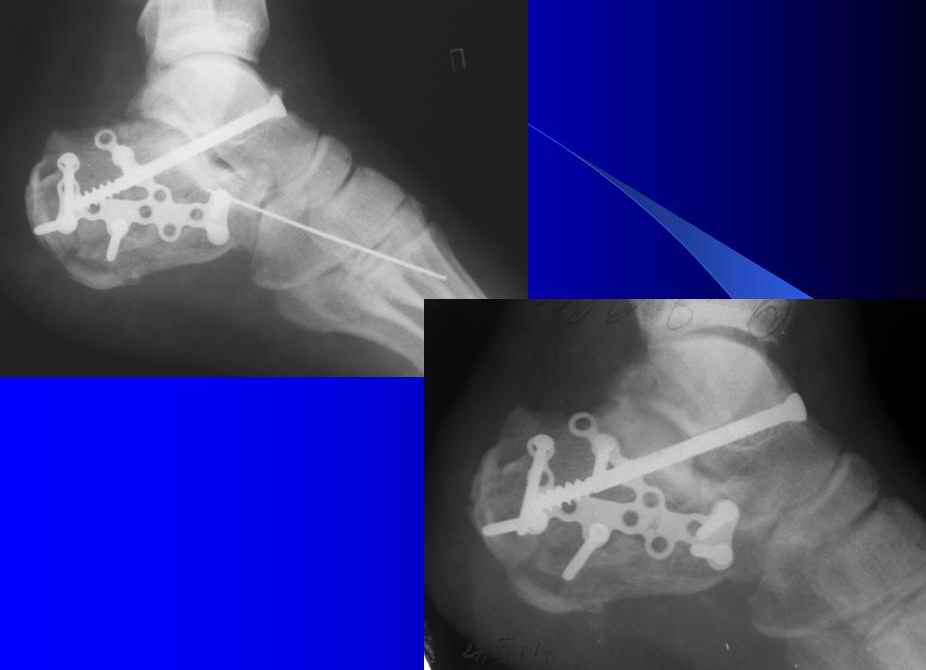

Re: Тяжелый перелом пяточных костей

Справа ситуация сложнее так как имеется помимо перелома имеется вывих тела пяточной костиПоэтому даже если удастся достигнуть хорошей репозиции необходимо сделать первичный подтаранный артродез.Иначе кость не будет держать в своём ложе.Но пластина нужна обязательно чтобы восстановить форму пятки.С уважением Дрягин